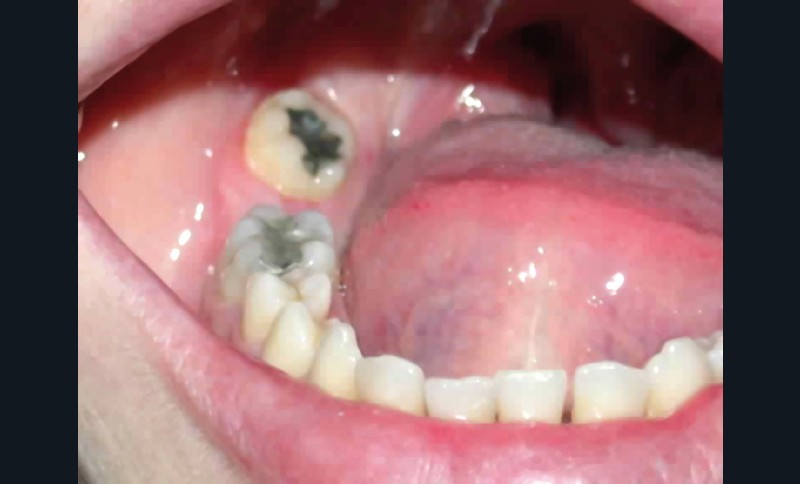

• anomalie de la forme d’arcade maxillaire, 47, 18 et 28 sont absentes. (fig. 1 à 8), 48 est positionnée très postérieurement, quasiment au niveau de la branche montante (fig. 9 et 11).

Sur le plan parodontal, il existe une gingivite résiduelle à une gingivectomie (la patiente étant sous anti-épileptiques).

Après assainissement parodontal, un traitement par expansion maxillaire avec vestibuloversion des incisives supérieures et mésialisation de 48 en lieu et place de 47 a été choisi. Il a été décidé d’extraire 38. Afin de permettre une reconstitution prothétique pour compenser la microdontie de 12 il est prévu de laisser un espace de part et d’autre de celle-ci, équivalent au diamètre mésio-distal de 22 soit 6,5 mm.